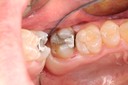

Kris Nip #19 pre-op

Kris Nip #19 amalgam removal